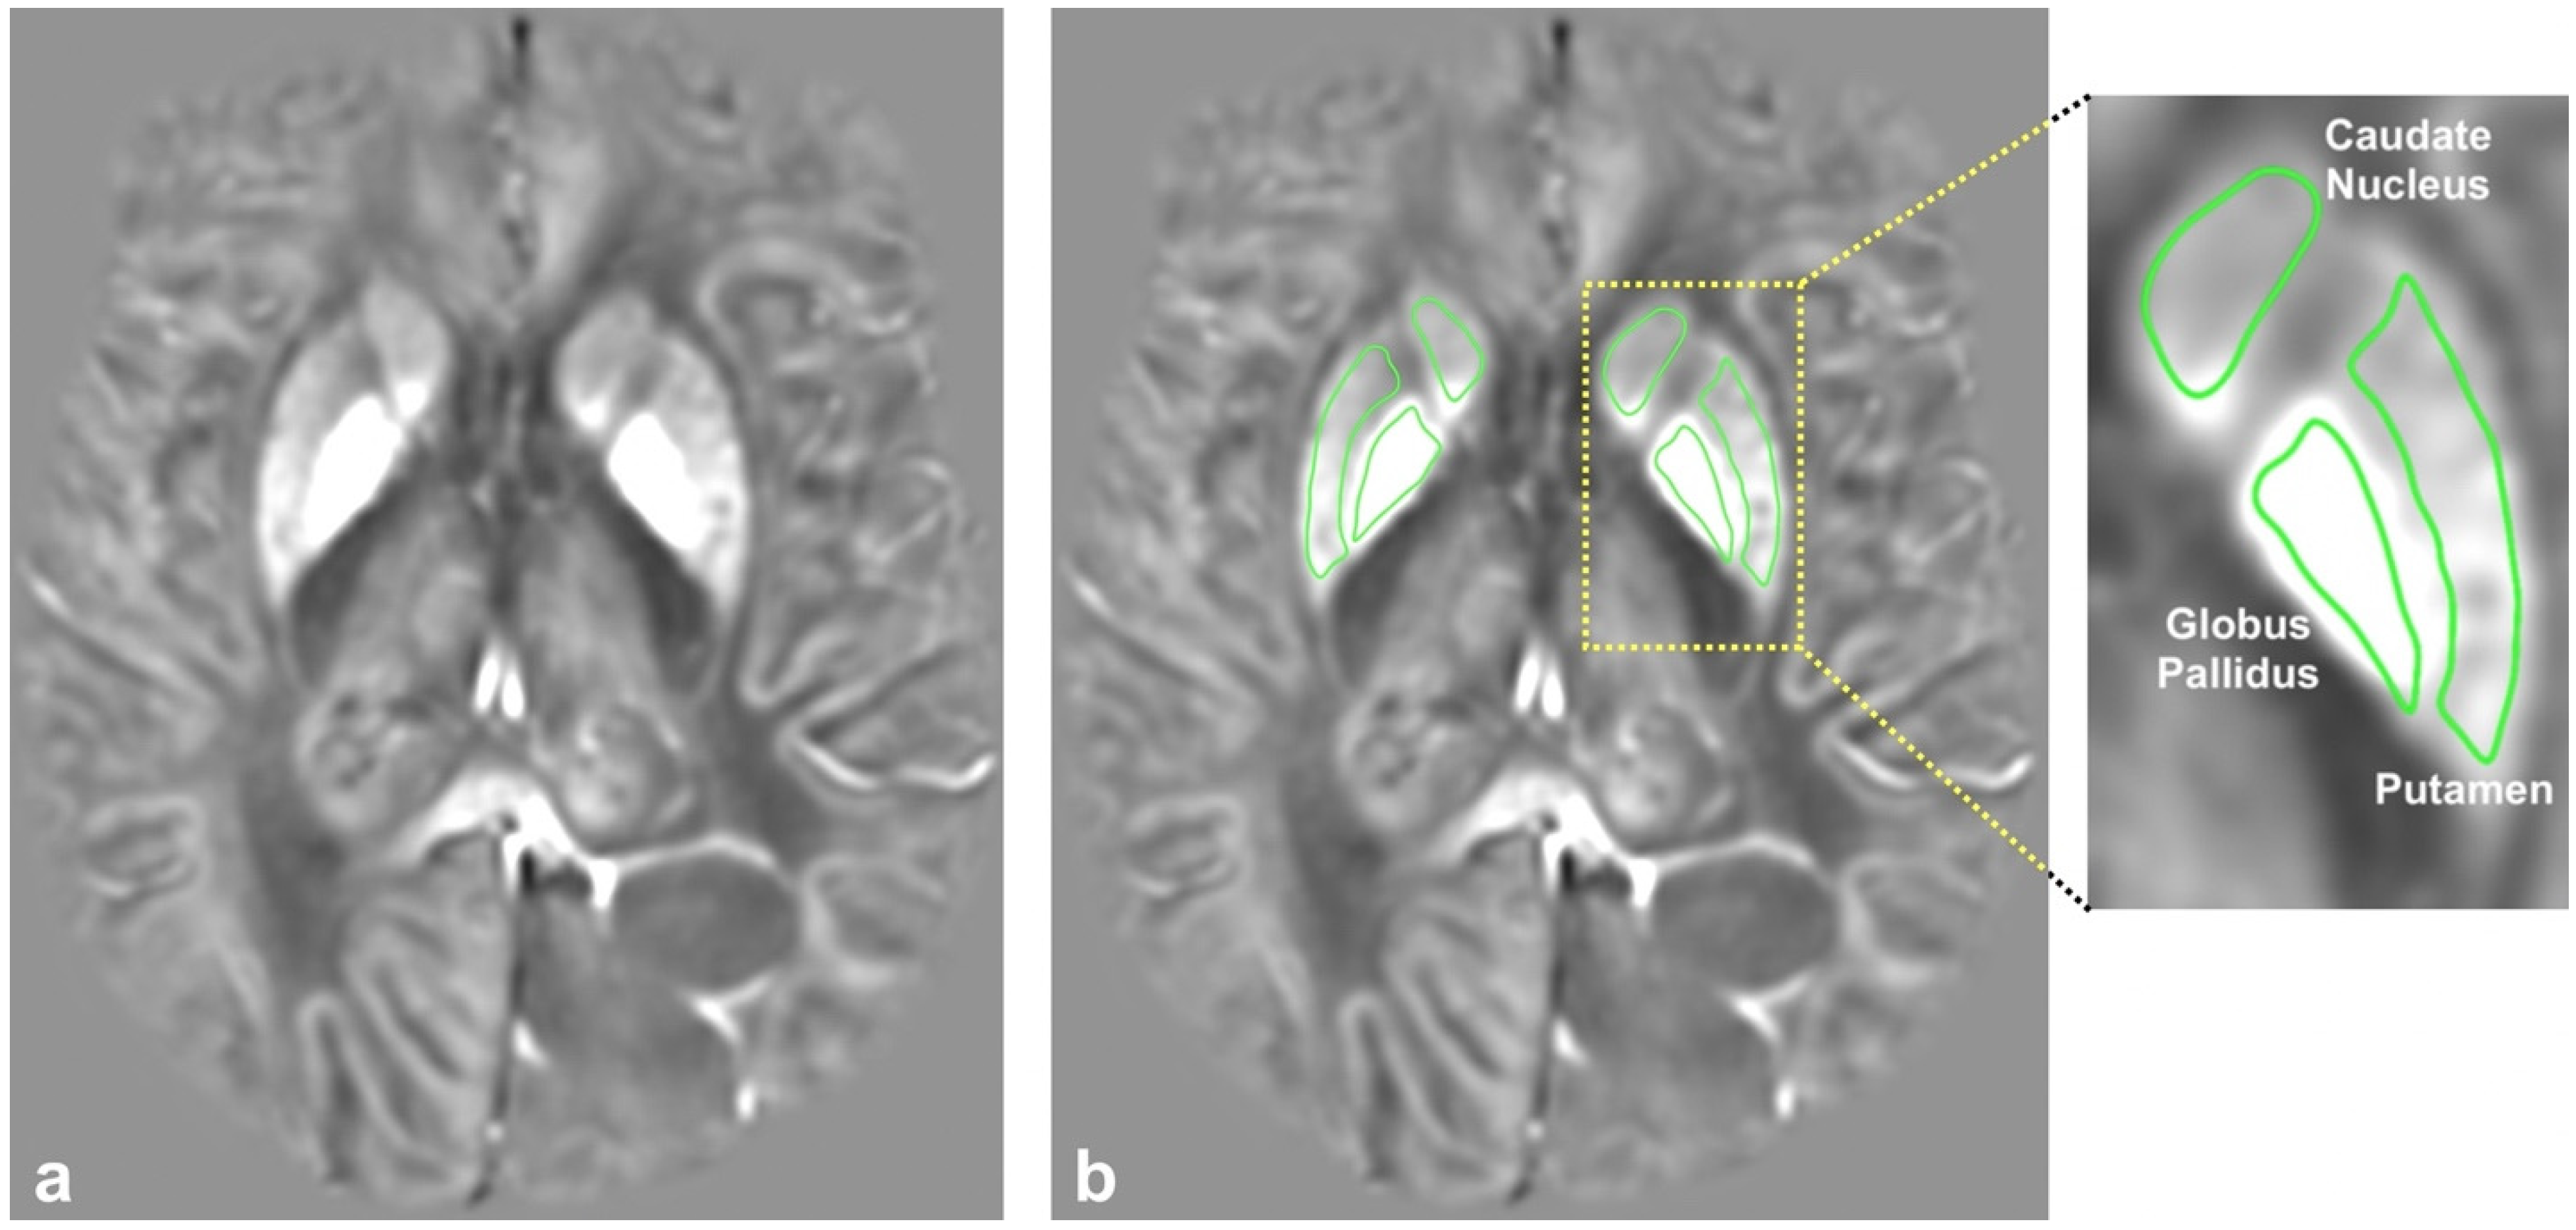

Image and Statistical Analysis: All image analyses were performed using the Horos medical imaging viewer (http://horosproject.org/ (accessed on 9 January 2022)). ROIs for the caudate, putamen, and globus pallidus were manually drawn onto the individual slices of the QSM images (Figure 1). The mean voxel intensities for all ROIs were averaged across multiple slices to obtain one QSM value per tissue region per patient. The resulting QSM values for the caudate, putamen, and globus pallidus were further averaged to obtain one overall BG (basal ganglia) QSM value for each patient.

Figure 1.

(a) A representative QSM image generated with QSMnet+ and (b) the same QSM image with the regions of interest (ROI) outlines. An enlargement of the left basal ganglia shows the labeled ROIs for the caudate nucleus, putamen, and globus pallidus.